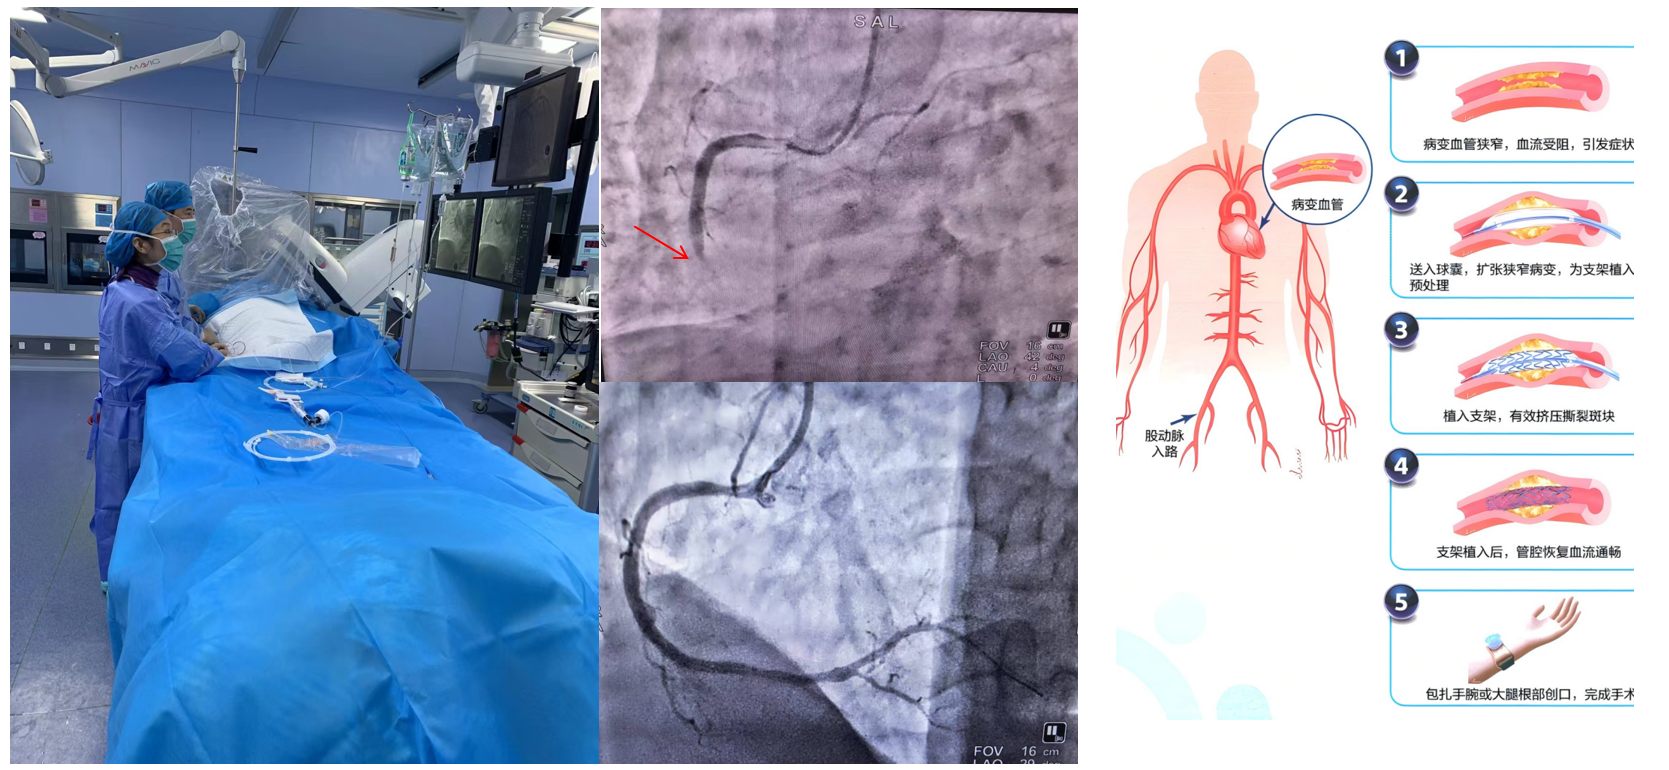

1.經皮冠狀動脈介入治療(PCI):是用心臟導管技術疏通狹窄甚至閉塞的冠狀動脈管腔,從而改善心肌血流灌注的一組治療技術。在血管嚴重狹窄或閉塞病變段放置支架或藥物球囊,以保證血管長期暢通,是冠脈介入手術的主流。

經皮冠狀動脈介入治療(PCI)